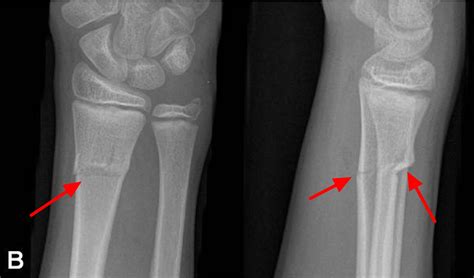

• Greenstick Fracture: More common in children, where the bone bends and cracks but does not break completely through.